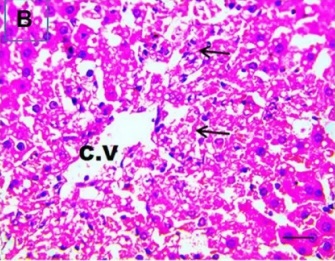

Put the liver tissue section under a microscope, and you can see that cisplatin can cause liver congestion (the blood that should return to the heart is blocked and stagnates in the hepatic veins), cell degeneration (vacuoles appear, which is the earliest change in cellular injury), apoptosis and necrosis, but these conditions can also be alleviated by using Ganoderma lucidum.

Figure 2 Effects of cisplatin and Ganoderma lucidum on hepatocytes